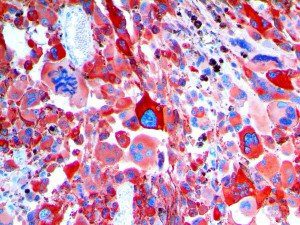

It is the ICU physician who is most likely to witness one of the deadliest manifestations of the abnormal immunological response, the cytokine storm syndrome (CSS). This response is also referred to by some as the cytokine release syndrome (CRS). CSS is characterized by continuous activation and expansion of macrophage and lymphocyte populations, which secrete large amounts of cytokines, causing the cytokine storm. This massive cytokine release is akin to hemophagocytic lymphohistiocytosis (HLH) disease, a syndrome characterized by initial unchecked and persistent activation of cytotoxic T lymphocytes and NK cells.

Clinical and laboratory manifestations of HLH include fever, enlarged liver and/or spleen, neurologic dysfunction, coagulopathy, liver dysfunction, cytopenias (i.e., low levels of erythrocytes, leukocytes, and/or platelets), hypertriglyceridemia, hyperferritinemia, hemophagocytosis, and eventually diminished NK cell activity as the immune system becomes progressively paralyzed. HLH can be familial (primary HLH) or secondary to another disease process (sHLH), such as rheumatic disease, in which it is referred to as macrophage activation syndrome (MAS, characterized by elevated ferritin).